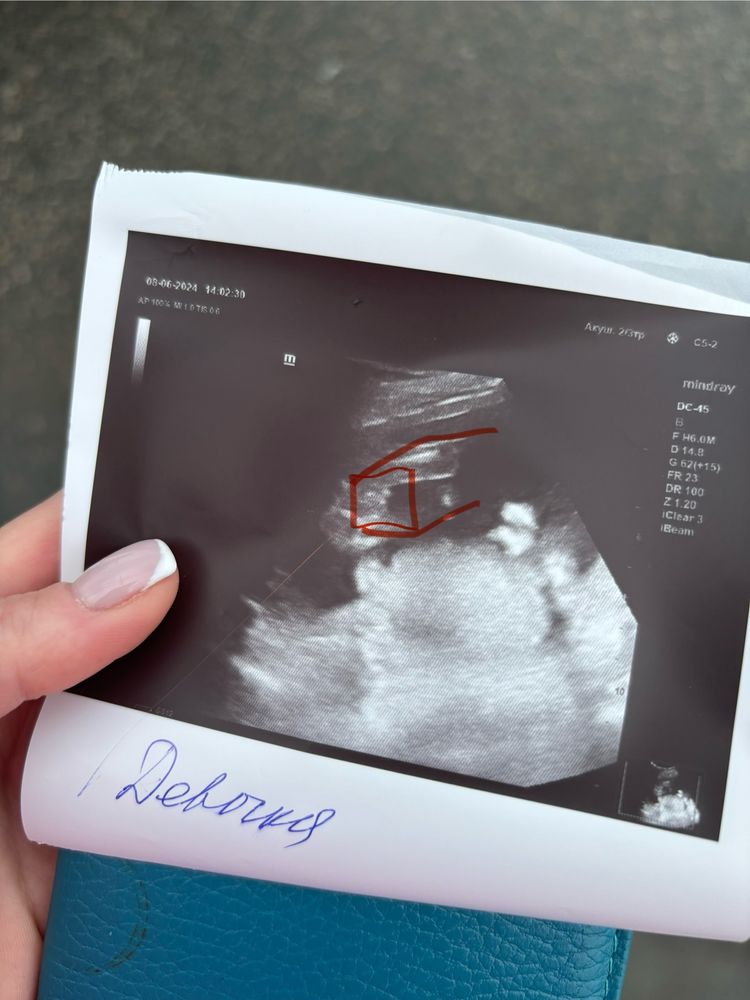

Натали, а как вам кажется, кто тут на узи? Изображение

Best mammy , не привычное изображение)) не буду гадать даже.

Если честно , я бы подумала что мальчик )) но я не врач ))) у моей девочки вообще все пусто было )))) 😅 только

Мне больше кажется что мальчик, ну кто я такая чтобы спорить с врачом 🤷🏻‍♀️😂

Я бы сказала мальчик. У девочек половая щель, тут не видно